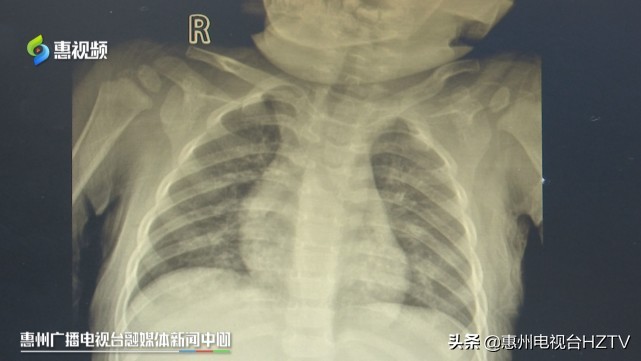

惠阳三和医院儿科主治医师 李顺辉:有点轻微的吸入性肺炎,但是通过一些对症处理之后,也恢复得还比较好。

医生介绍,柴油、汽油和机油都属于有机烃类混合物,小儿误服或者吸入高浓度柴油、汽油,机油蒸气可引起有机烃中毒,通常情况下,急性中毒主要影响肺、中枢神经系统和心脏三个靶器官,临床表明5岁以下儿童误服大量有机烃类混合物可引起致命的严重肺损伤,导致中毒性肝炎和肾炎等。